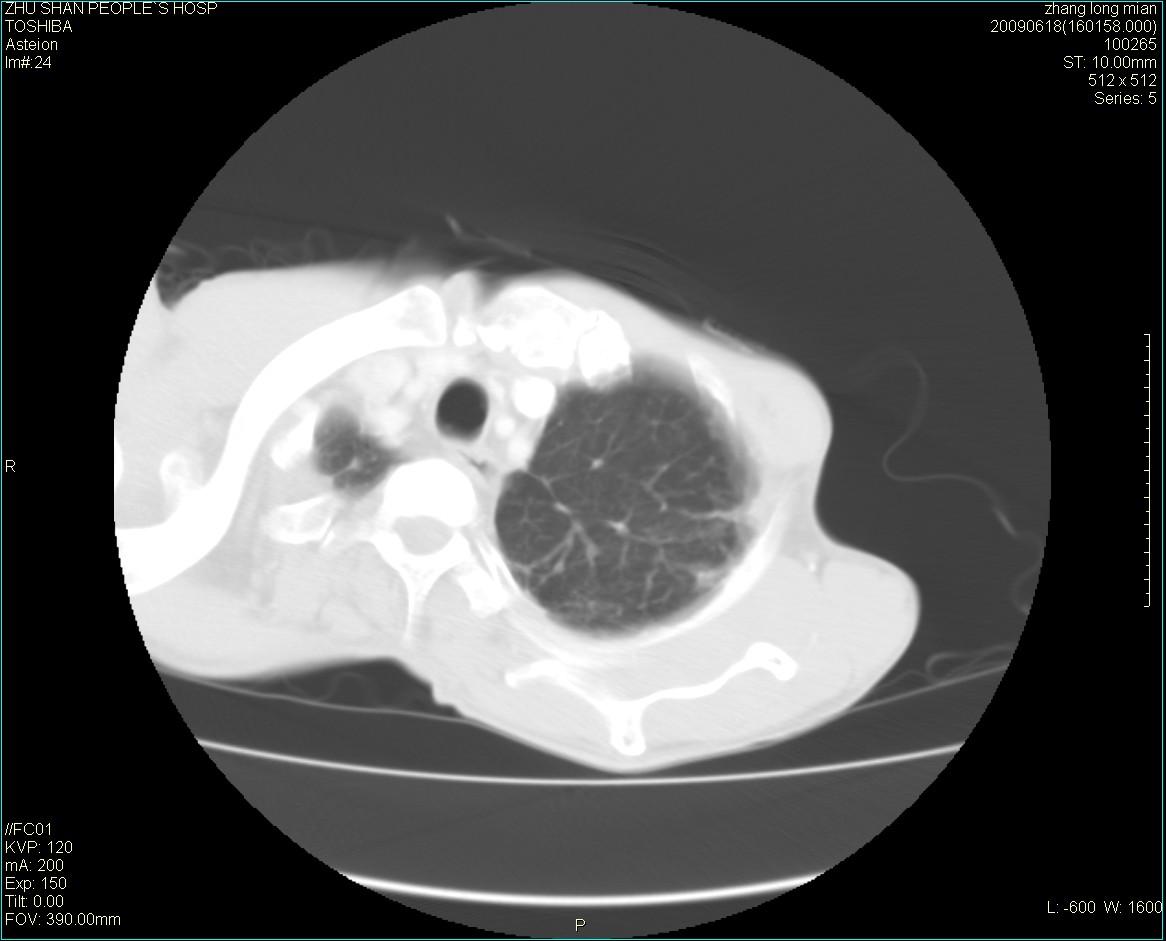

男性 65岁 胸片发现右下肺包块.诊断肺ca并纵隔转移没有问题吧!

两侧胸廓不对称,右侧呈塌陷改变,右肺萎缩。

右下肺见浅分叶状软组织块影,边缘有毛刺,其下部似见不完整偏心空洞影,邻近胸膜凹陷征,并胸腔积液。

增强见纵隔区气管隆突上下及左肺门区肿大淋巴结。左肺感染性病灶。

另见右上肺见一枚小结节影,性质待定。